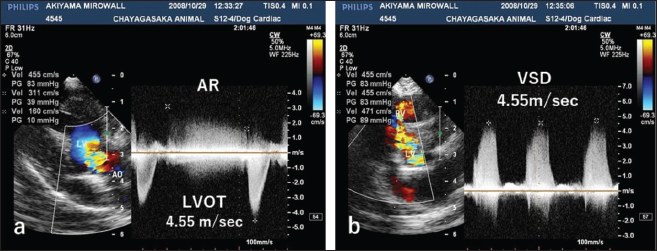

Auscultation revealed a heart rate of 150 beats/minutes and a grade 4/6 systolic murmur in the precordial region near the sternum. Electrocardiography revealed a mean electrical axis of +82º and a mitral P wave in the II, III, and aVF leads. Thoracic radiography showed moderate heart enlargement (vertebral heart score, 10 vertebrae; cardio-thoracic ratio [CTR]: 70%) and increased opacity of the pulmonic field. B-mode echocardiography revealed a small polypoid mass at the dorsal part of the interventricular septum below the aortic valve (Fig. 1a). Two areas of flow acceleration were evident, leading to the mosaic pattern on colour flow Doppler echocardiography: one due to a membranous VSD of 3.17 mm in diameter and the other due to LVOT obstruction caused by the mass (Fig. 1b). In the continuous-wave Doppler (CWD) mode, the LVOT blood flow velocity was 4.55 m/seconds, with a calculated systolic pressure gradient (ΔP) of 83 mmHg between the left ventricle (LV) and aorta (Fig. 2a), and the VSD blood flow velocity was 4.55 m/seconds, with a calculated systolic ΔP of 83 mmHg between the LV and right ventricle (RV) (Fig. 2b). Aortic regurgitation (AR) (Fig. 2a) was also observed. In the CWD mode, the AR blood flow velocity was 3.11 m/seconds, with a calculated diastolic ΔP of 39 of mmHg between the aorta and LV (Fig. 2a).

Fig. 2. CWD echocardiography of the right parasternal long-axis view. (a) The blood flow velocity in the left ventricular outflow tract (LVOT) was 4.55 m/seconds, with a calculated systolic pressure gradient (ΔP) of 83 mmHg between the LV and aorta (AO). The AR blood velocity was 3.11 m/seconds, with a calculated diastolic ΔP of 39 mmHg between the LV and AO. (b) The blood flow velocity in the ventricular septal defect (VSD) was 4.55 m/seconds, with a calculated systolic ΔP of 83 mmHg between the LV and RV. The peak velocity measurement of LVOT, AR, and VSD is not accurate, because of measurements taken using the “beard” instead of the “chin” (see “Study Limitations”).

Fig. 4. CWD echocardiography after surgery. (a) Five days after surgery, the systolic pressure gradient (ΔP) between the LV and aorta (AO) had decreased from 83 mmHg (the preoperative value) to 40 mm Hg. The corresponding values for left ventricular outflow tract (LVOT) velocity were 4.55 and 3.17 m/seconds, respectively. (b) Thereafter, the values were essentially unchanged and were 48.7 mmHg (ΔP) and 3.49 m/seconds (LVOT) at 8.5 months.

The dog was monitored daily with physical examinations, including echocardiography, and the postoperative course was good. However, the dog remained in our hospital for 10 days until discharge to accommodate the owner, who lived remotely. Postoperative auscultation revealed a persistent grade 2/6 systolic murmur, and colour Doppler echocardiography revealed slight residual shunt blood flow through the VSD. As shown via thoracic radiography, the CTR was lower after surgery (66% at 10 days and 65.9% at 8.5 months) than before surgery (70%). As shown via CWD echocardiography, the systolic ΔP between the LV and aorta was also lower after surgery (40 mmHg at 5 days) than before surgery (83 mmHg) (Fig. 4a); after 5 days, it remained essentially unchanged and was 48.7 mmHg at 8.5 months (Fig. 4b). At 8.5 months, the dog had no clinical signs of heart disease and her body weight had increased to 3.9 kg. According to the referral hospital, the dog had no cardiac complications during the next 11 years.

In our study, CWD echocardiography was especially useful for monitoring blood flow velocity by calculating ΔP before and after surgery. As determined using this modality, the systolic ΔP between the LV and aorta was 83 mmHg immediately before surgery. According to the referral hospital, it was 50.7 mmHg 2 months before surgery. This slow increase in the ΔP presumably reflected the slow growth of the tumour, which was likely benign (Han et al., 2012). Five days after surgery, the ΔP had decreased to 40 mmHg (Fig. 4a), with little change over the next 8.5 months (Fig. 4b). Although echocardiography may indicate whether a tumour is benign or malignant, biopsy is required for definitive diagnosis of a cardiac myxoma.

For CWD echocardiography, Kyranis et al. (2018) identified the measurement site for peak velocities on Doppler wave to ensure the exact value is taken at the “chin” and not the “beard”. In this case (Fig. 2a and b), we measured the peak velocities at the beard, not the chin. Therefore, the exact volume appears to be slightly lower. However, this cannot be corrected because of a lack of original image data. On echocardiographic assessment of the LVOT, pulsed-wave Doppler (PWD) is used for LVOT flow evaluation when no flow acceleration is noted to accurately measure the specific velocity at the region of interest. When there is a fixed obstruction or dynamic obstruction (as is possible in this case owing to the mobile mass) leading to flow acceleration, then aliasing of PWD can occur, which forces us to use CWD for evaluation of the peak velocity and peak gradient (Koplitz et al., 2006). However, in our case, we did not obtain PWD data.